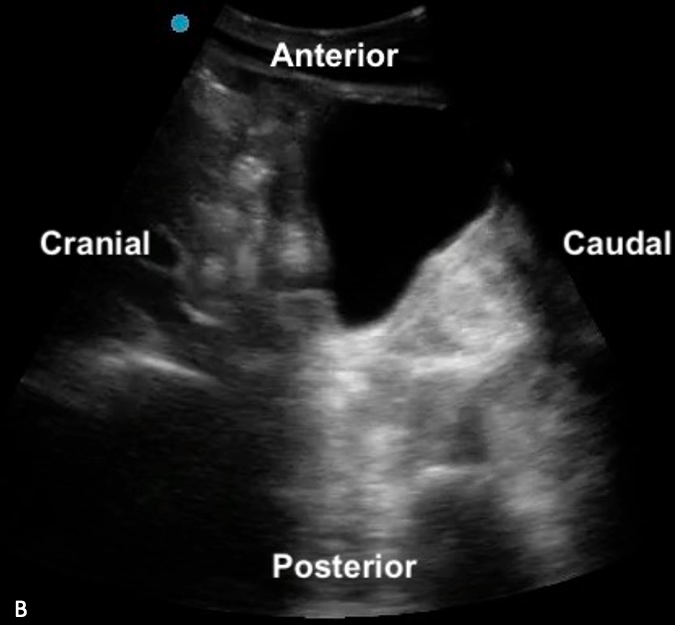

When scanning the bladder, like with any ultrasound, the transverse plane provides a cross-sectional view, with patient right on the screen’s left, patient left on the screen’s right, and anterior in the near field and posterior in the far field. In the sagittal plane, cranial is on the screen’s left, caudal is on the screen’s right, with anterior in the near field and posterior in the far field.

Figure 5ab: Transverse and sagittal bladder views with orientation labels

The shape and relationships of the bladder on ultrasound examination will depend on its degree of filling. The sagittal view is triangular (figure 10), and the transverse view is rectangular (figure 11). That said, the shape varies depending on bladder fullness. When distended, the bladder walls appear thinner compared to a thicker appearance when less distended (figure 12).

Figure 10: Normal bladder in the sagittal plane